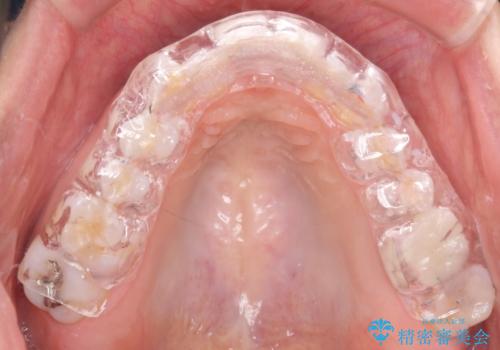

歯を保護するためのナイトガードを装着していきます。

厚みのあるナイトガードを調整することで、夜間の歯ぎしりにより歯にかかる強い力を分散させることができます。